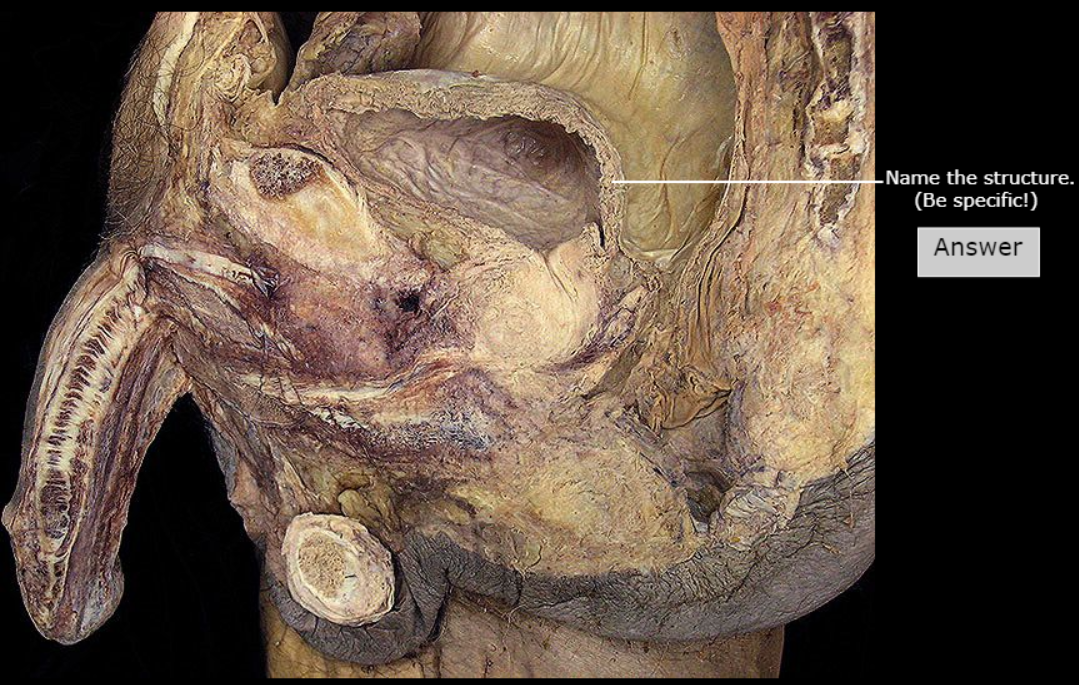

Prostate